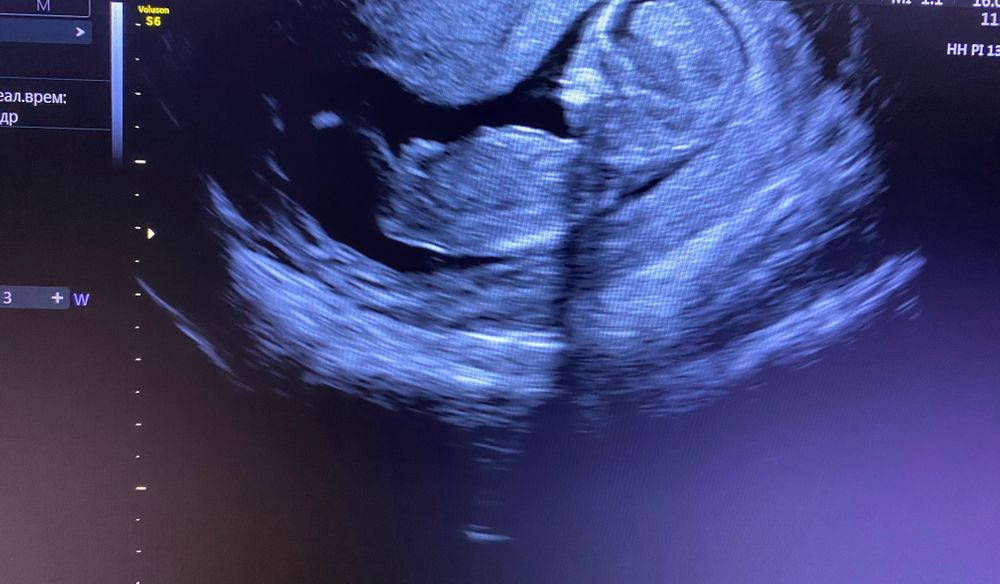

1 скрининг

Мы с Вами почти на одном сроке: 8го числа делада скриниг 12 недель;) Пол врач сказал на таком сроке не виден... Но на следующем узи уже узнаете;)) Я немного раньше узнаю, т.к. сдали НИПТ, вот жду еще неделею...с замеранием сердца

По-моему , мальчик )

Девочка, но не точно)

Не видно. Фото и, правда, немного со спины, а нужно точно в профиль, чтобы рассмотреть половой бугорок.

Умеренное расширение лоханок плода. Очень переживаю!!! Расширено твп